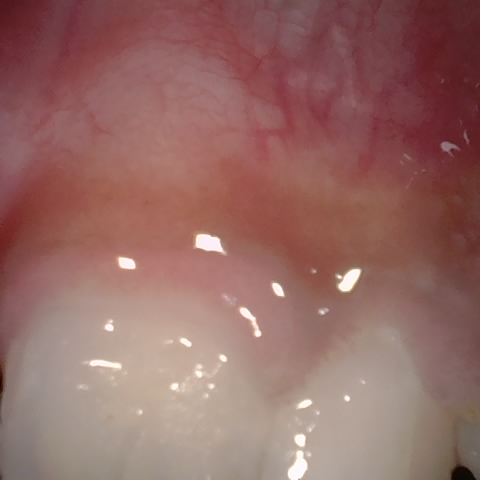

Annotated as "Bad"